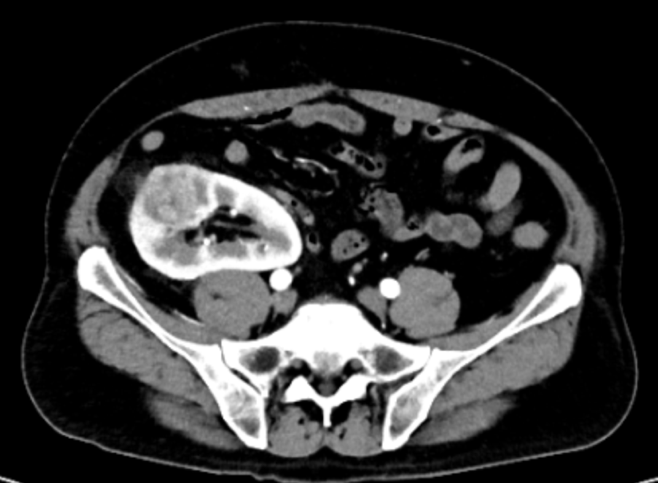

(CT影像:右侧移植肾肿瘤)